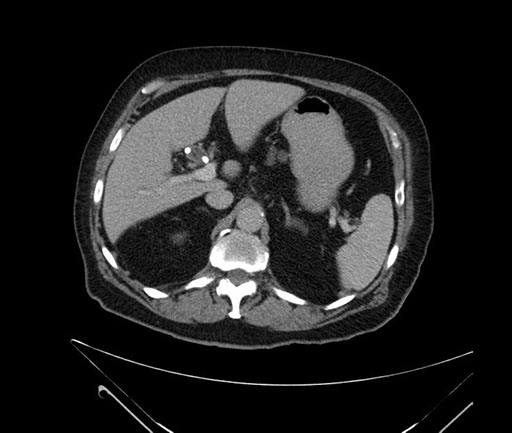

Whipple (pancreaticoduodenectomy) [case 7]

Axial - stented

Imaging analysis

Based on your CT findings, which issue(s) would give reason for "planned slowing down moment(s)" in this case?

Considering a standard Whipple procedure, what step(s) of the operation would you do differently in this case?